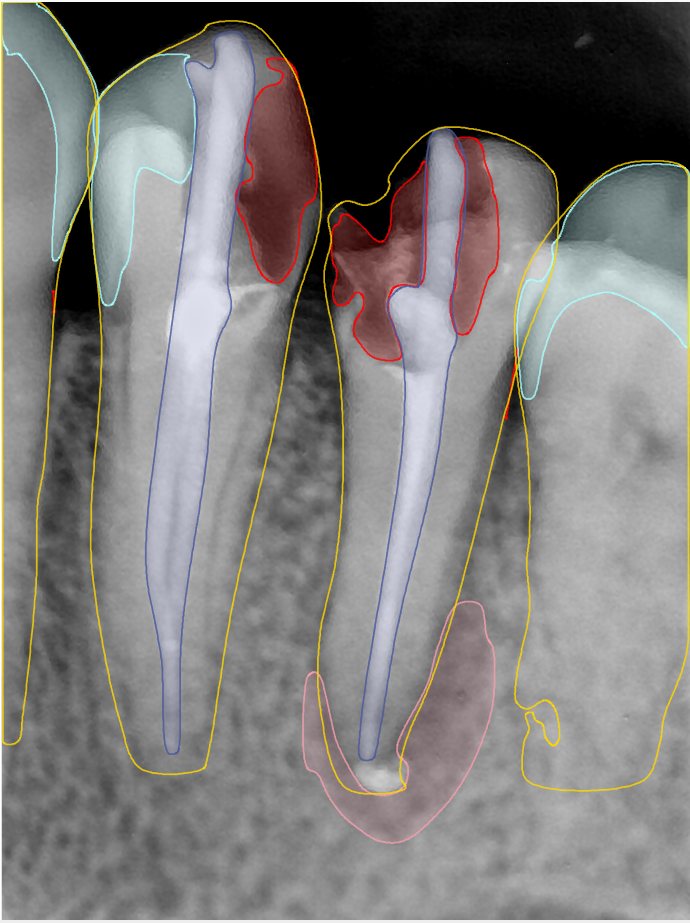

CR/DR 牙齿分割阶段记录

当前进展

- 完成了 CR/DR 牙齿相关分割训练

- 当前结果已经达到阶段预期,但仍有细节问题需要继续处理

相关测试

遇到的问题

- 训练过程中出现过 mask 下移问题

- 部分结果会出现 box 填充异常

- mask 边缘仍然有比较明显的锯齿感

参考

第二版算法问题测试